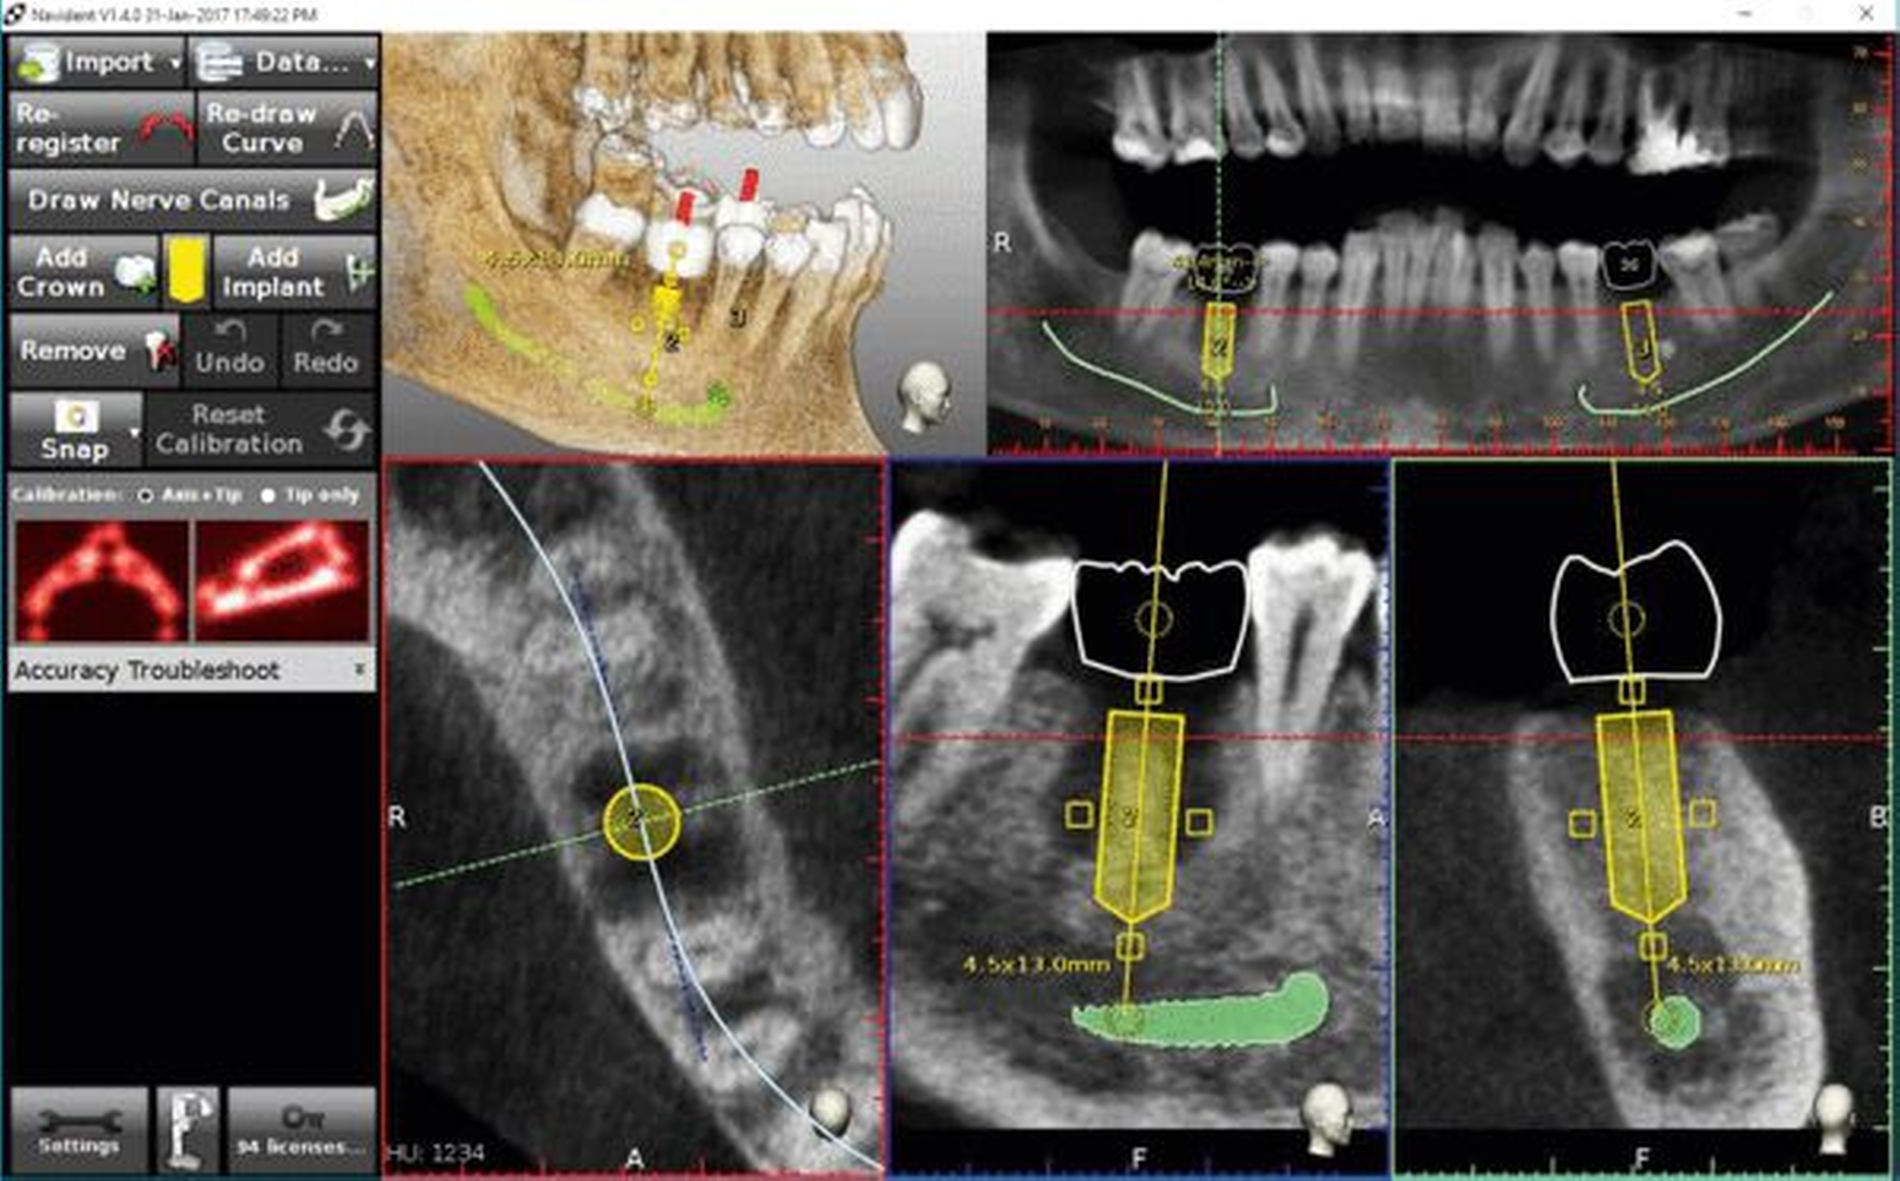

Obwohl die Auflösung (in Linienpaaren) gegenwärtig noch unterhalb der Auflösung für ein konventionelles Orthopantomogramm (OPTG) liegt und die DVT nicht zur Routinediagnostik angewendet werden darf, bietet sie durch die Option einer dreidimensionalen Betrachtung anatomischer Strukturen in vielen Fällen diagnostische Vorteile. Beispielsweise kann die optimale Position eines Implantats in einem atrophierten Kieferkamm digital bestimmt und der spätere Knochen-Implantat-Kontakt vorhergesagt werden (Abbildung 5). Weiterhin kann im Unterkiefer bei einer Implantatplanung ein Sicherheitsabstand von in der Regel 1,5 mm zum Nervus alveolaris inferior berücksichtigt werden. Dies ermöglicht es, die bestehende Knochenhöhe soweit möglich auszunutzen und zugleich das Risiko eines Sensibilitätsverlusts durch eine Nervschädigung zu minimieren. Weiterhin kann ein Augmentationsbedarf anhand der Darstellung des Knochenangebots vor Behandlungsbeginn abgeschätzt werden, so dass Patienten ebenfalls über die Darstellung der Defektsituation nachvollziehen können, warum die vorgeschlagene Behandlungsmethode notwendig ist.

Besonders im Unterkiefer besteht zudem die Gefahr einer lingualen Perforation bei Bohrung des Implantatbettes und Insertion des Implantats, da sich die Kortikalis in diesem Bereich typischerweise verjüngt. Aus diesem Grund kann die vorherige Simulation unter Berücksichtigung von Implantatlänge und -durchmesser sowie der anatomischen Gegebenheiten gerade für Einsteiger von Vorteil sein und das Komplikationsrisiko verringern.

Möchte man eine wie in Abbildung 5 dargestellte Planung per Schablone auf den Patienten übertragen, ist eine Überlagerung (Matching) der DVT-Aufnahme mit einem digitalen Modell des Patienten erforderlich.

In Abbildung 7 ist dargestellt, wie die Position zweier Implantate digital geplant und im Anschluss eine Bohrschablone („partially guided“-Konzept) erstellt wurde. Nach dem 3-D-Druck der Schablone wurden Führungshülsen in der entsprechenden Position eingebracht.